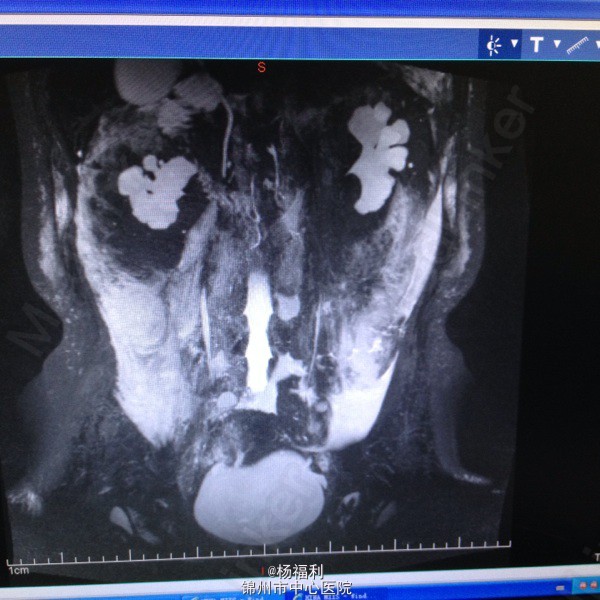

44岁女患。为消化科我会诊患者。 现病史:以上腹痛9小时为主诉入院。无发热及寒战、噁心未呕吐,无腹泻及黑便。 既往史:双眶炎性假瘤2年,口服激素治疗,并补钾。

查体:上腹部压痛,无反跳痛、右侧压痛明显,右肾区叩击痛,左肾区轻叩击痛,双输尿管走形区无压痛。 辅助检查;泌尿系彩超:双肾积水。 血白细胞:9.99*10^9。 肾功能正常。 全腹部ct及MRU检查:见图片。

诊断;真的不知道是啥病。 处理:暂时止痛处理。双肾病变。不知从哪里下手。

讨论:患者疾病和眶部肿瘤有关系吗? 和激素应用有关系吗? 最后建议患者去北京大医院进一步诊断治疗。 大神快快现身。